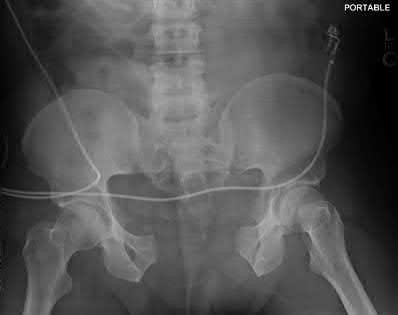

A 44-year-old male presents after being struck by a car. He is hypotensive, and has an obvious open tibia and a closed femoral shaft fracture. A pelvic radiograph is obtained and shown in Figure A. A representative CT scan image in shown in Figure B. The patient is placed in a pelvic binder, and his blood pressure normalizes with crystalloid and a blood transfusion. He then undergoes pelvic angiography, and his internal iliac artery is embolized. Which of the following definitive treatment options is most appropriate in this case?

The radiographs and CT scan show a fracture pattern consistent with an APC-III injury. This is most appropriately treated with pubic symphysis ORIF with a multi-hole plate and posterior iliosacral screw fixation.

APC-III pelvic ring injuries are associated with with disruption of the anterior and posterior SI ligaments (SI dislocation) as well as disruption of

sacrospinous and sacrotuberous ligaments. They are commonly associated with vascular injury and retroperitoneal bleeding.

Illustrations A, B, and C show the AP, outlet, and inlet postoperative radiographs.